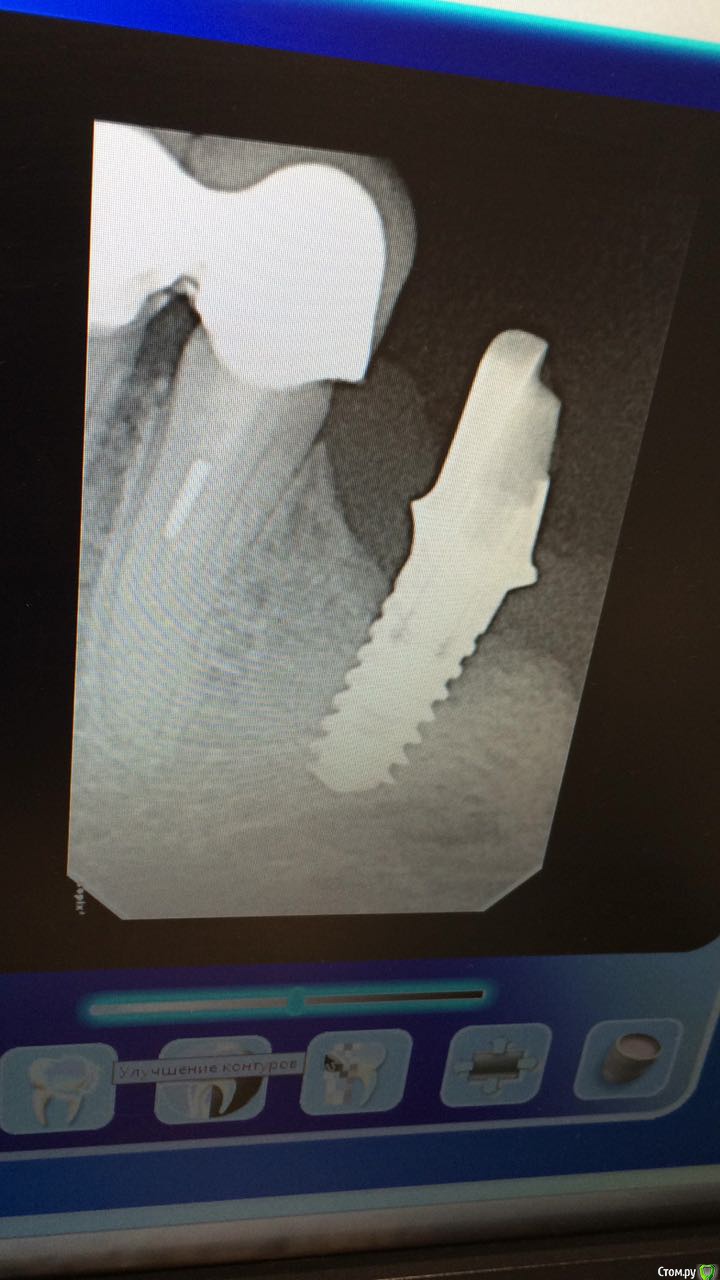

Уважаемые доктора, после установки 34,36,37 имплантатов появилась пульсирующая боль, по результата оптг, (ушла кость)было принято решения удалить 36 имплант,имплант был хорошо интегрирован , воспалительного процесса небыло,после удаления

пульсация сохранилась, может ли быть причиной 33 зуб, где сломан файл,есть ли там кариес?